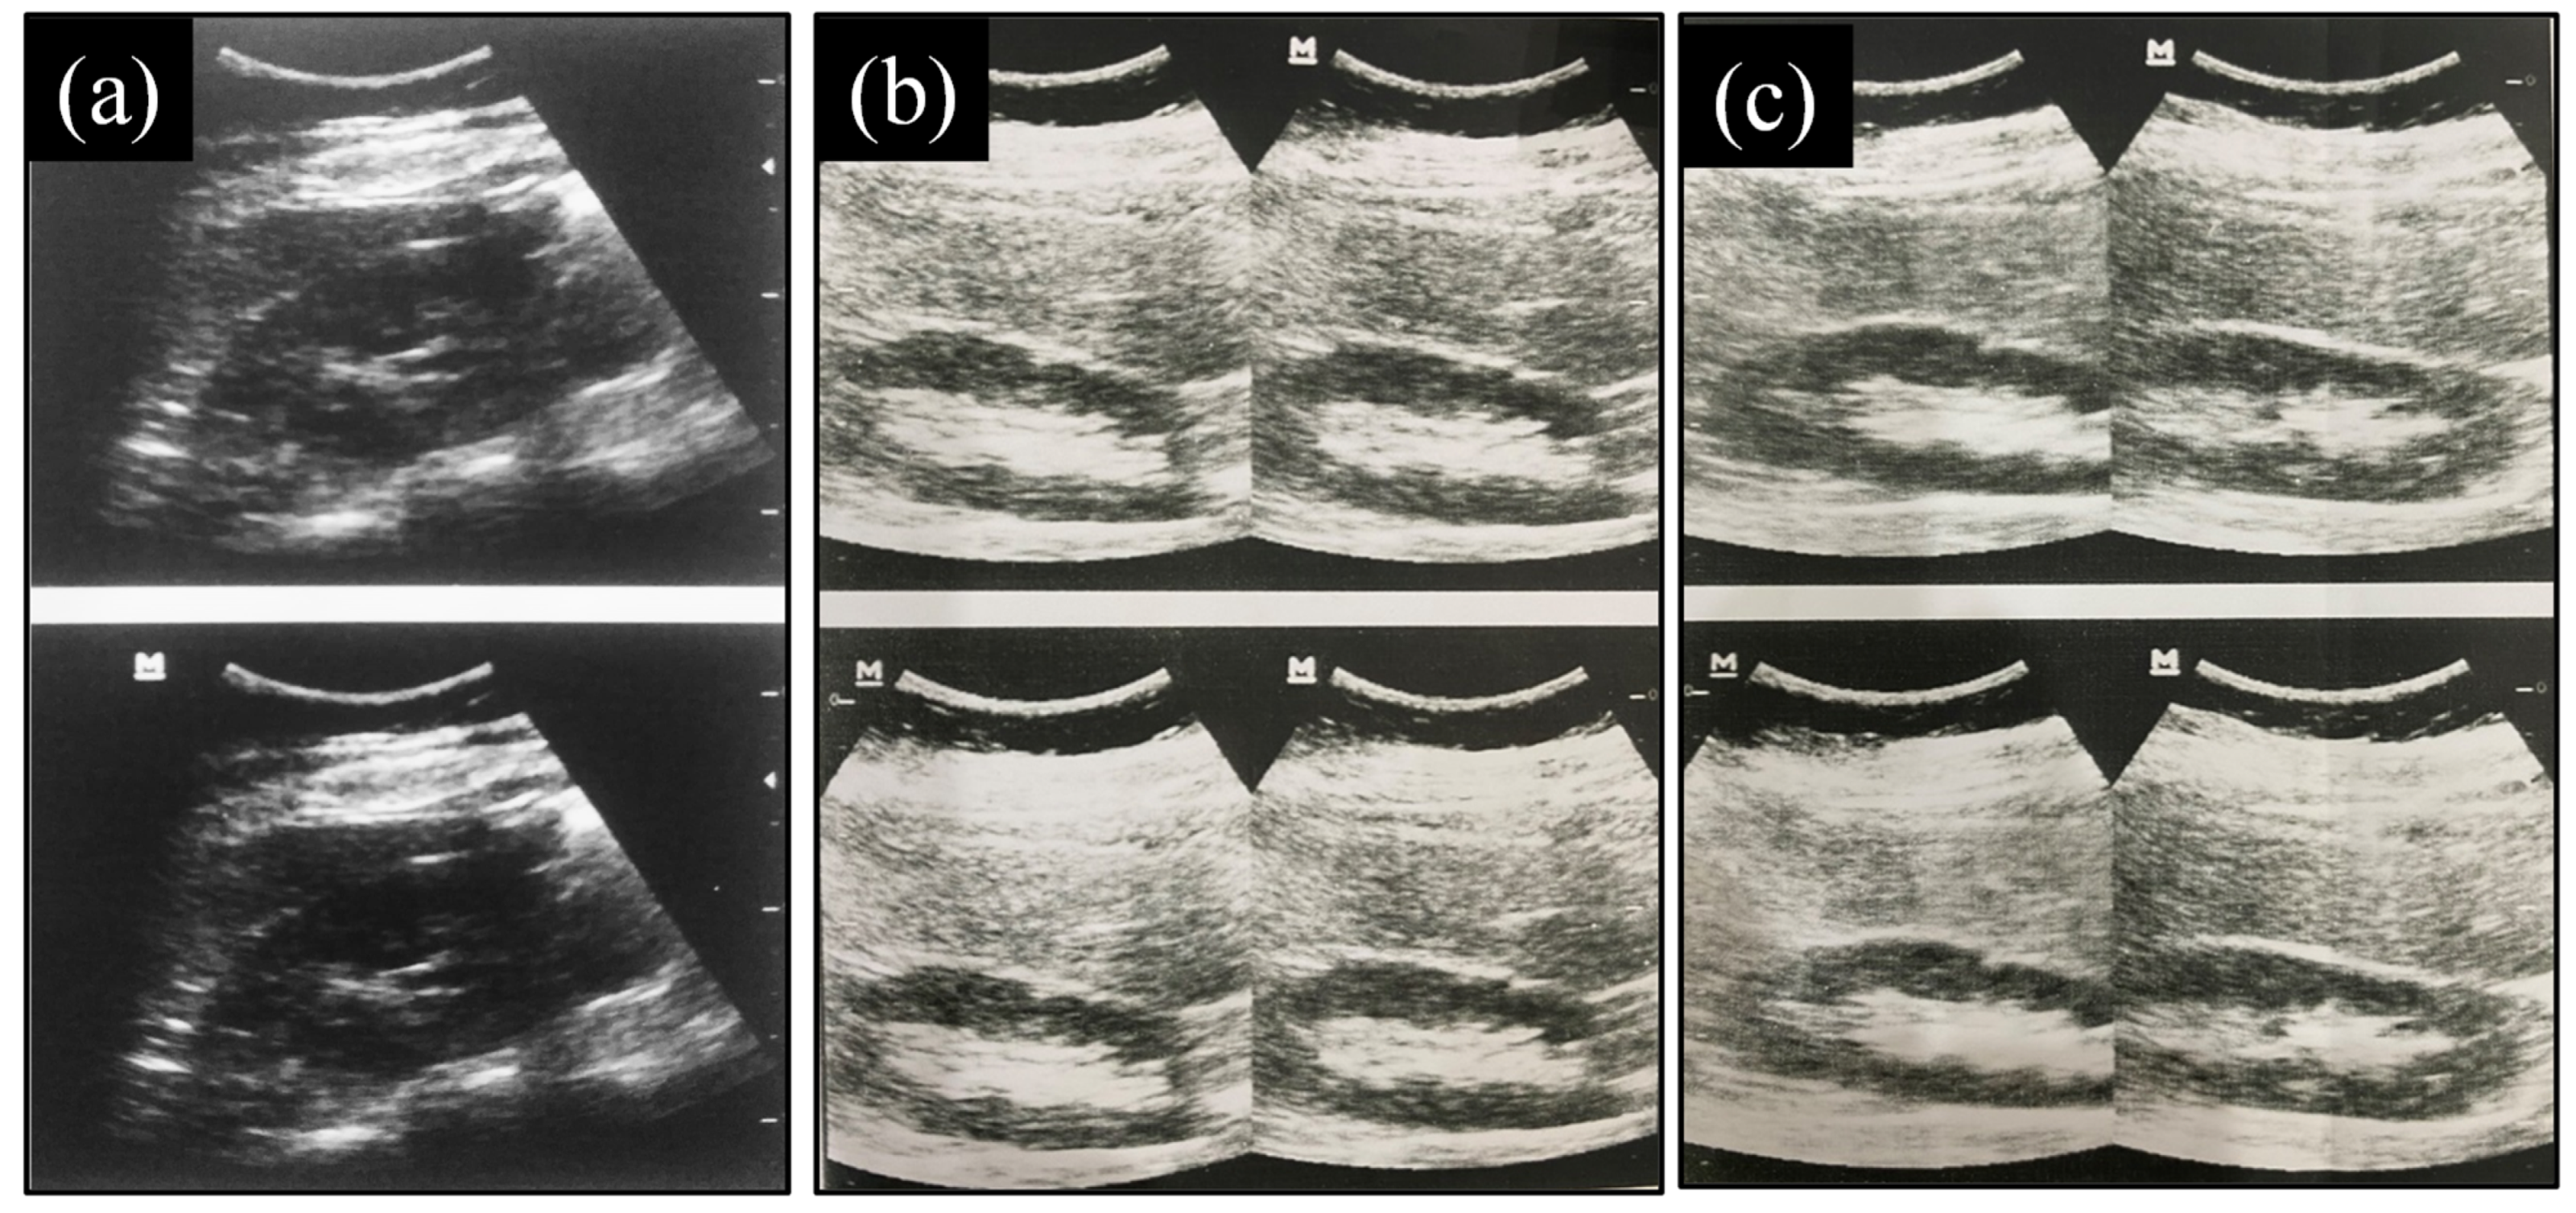

2.9.3. Evaluation of Images Produced

3.9.3. Evaluation of Images Produced